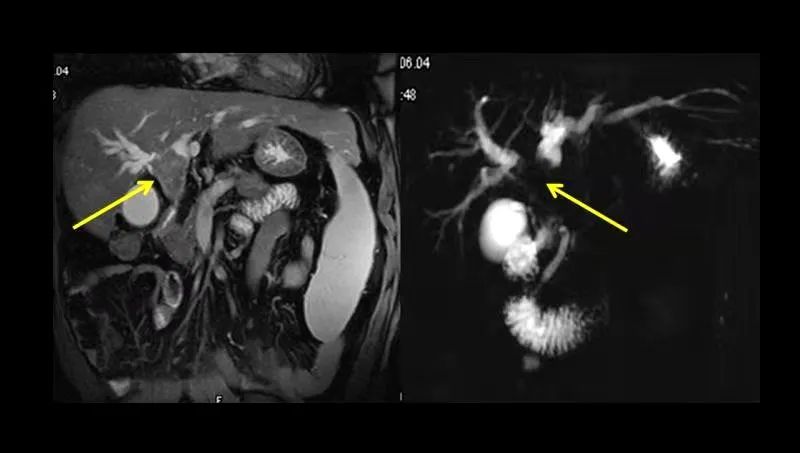

肝左叶肿瘤,局部胆管扩张

胆总管下端结石CT和MRCP图

肝门部肿瘤MRI和MRCP图

MRCP,也叫磁共振胰胆管成像,是磁共振一种特殊成像方法,能快速直观地对整个胆道系统进行成像,可一目了然了解胆道疾病的部位和程度,现已广泛应用于临床。